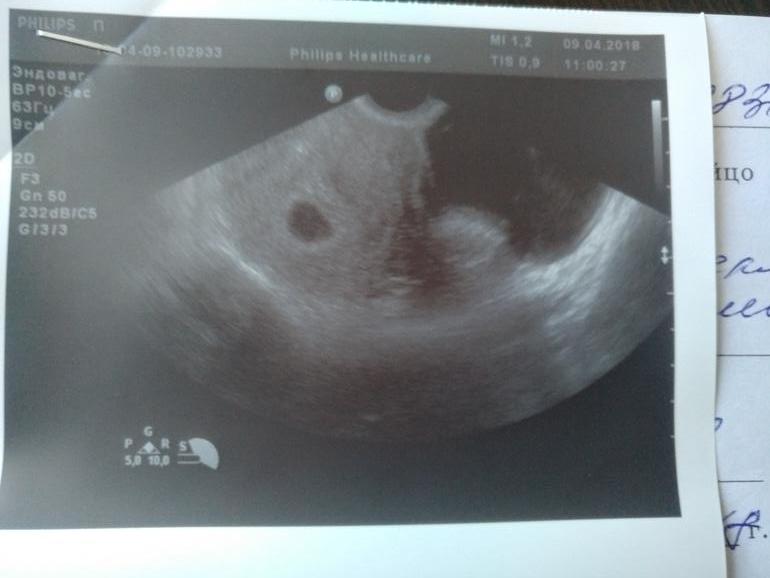

Вопросы про УЗИ, обследования и анализы: что, где, как, когда?Привет, девочки. Ходила сегодня на узи сегодня... плодное яйцо хорошее, жёлтое тело прям настоящее, как врач сказала. А вот эмбриона не увидели....как так?!

ХГЧ рос прекрасно, почему не виден эмбрион??!! Цикл 28 дней четко! Тесты яркие.

Тааак а теперь тадааам!!! Поехали мы переделать УЗИ платно...посмотрели кровоток, показали "кардиограмму" сердечка, эмбрион 4.6 мм, все на месте и соответствует сроку 6 недель!!!!!!

УЗИ эмбрион 4.6 мм плодное яйцо 8-1.3 мм

желточный мешочек 3.7 мм хорион кольцевидный